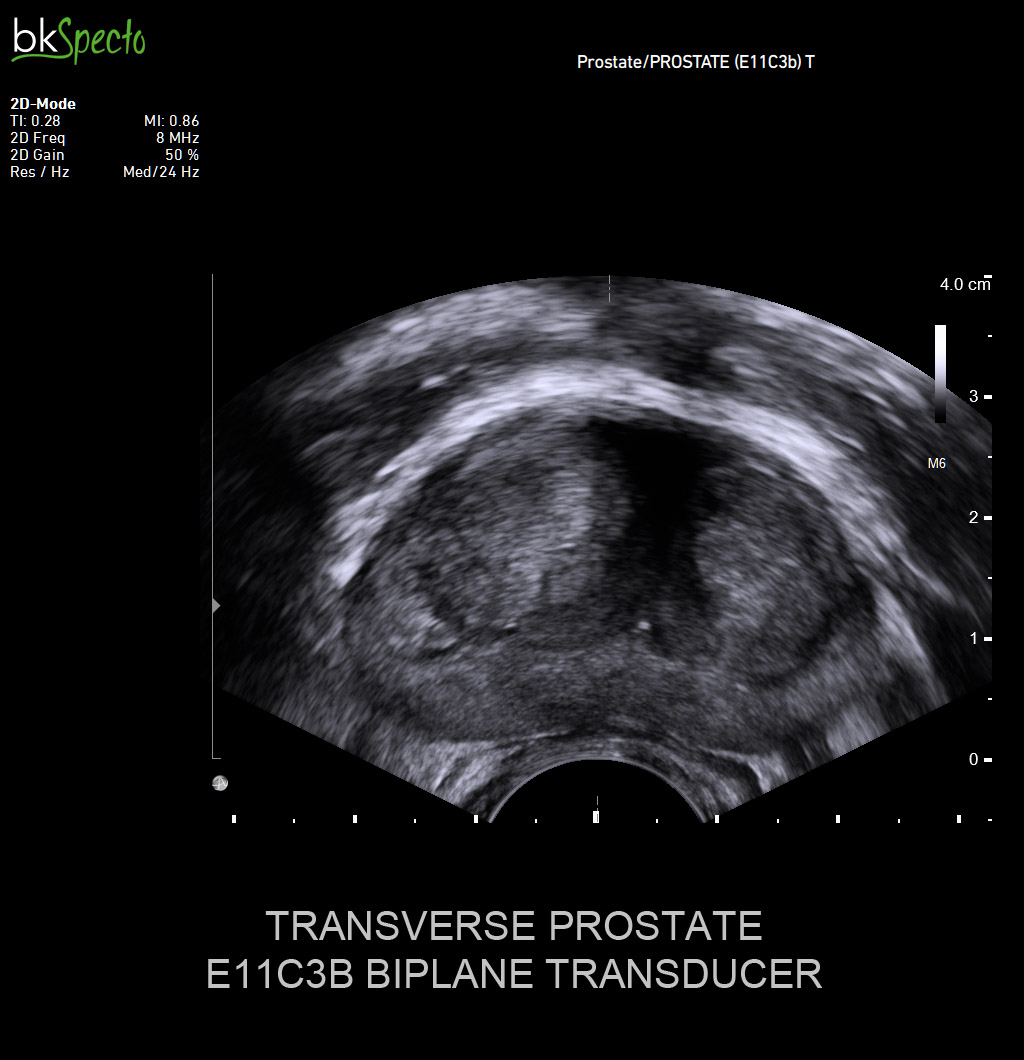

- Modul sinh thiết và điều trị u xơ tiền liệt tuyến (TUR) qua ngả trực tràng dưới dướng dẫn siêu âm _Prostate Imaging & Biopsy: Đặc biệt kỹ thuật điều trị u xơ tiền liệt tuyến bằng hạt phóng xạ (brachytherapy)

- Gá sinh thiết dùng với đầu dò siêu âm các loại